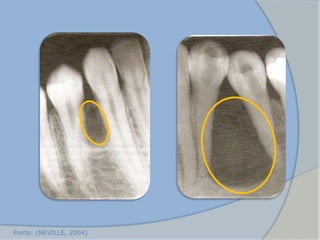

• Características

radiográficas

 Lesão radiotransparente unilocular associada à coroa.

 Os cistos dentígeros podem deslocar o dente.

 A reabsorção dos dentes adjacentes erupcionados pode ocorrer.

 Cistos infectados podem mostrar limites mal definidos.

 O diagnóstico não deve ser somente baseado em evidências

radiográficas, pois, os ceratocistos odontogênicos, ameloblastoma

uniloculares e outros tumores podem ter imagens idênticas.

(NEVILLE, 2004)